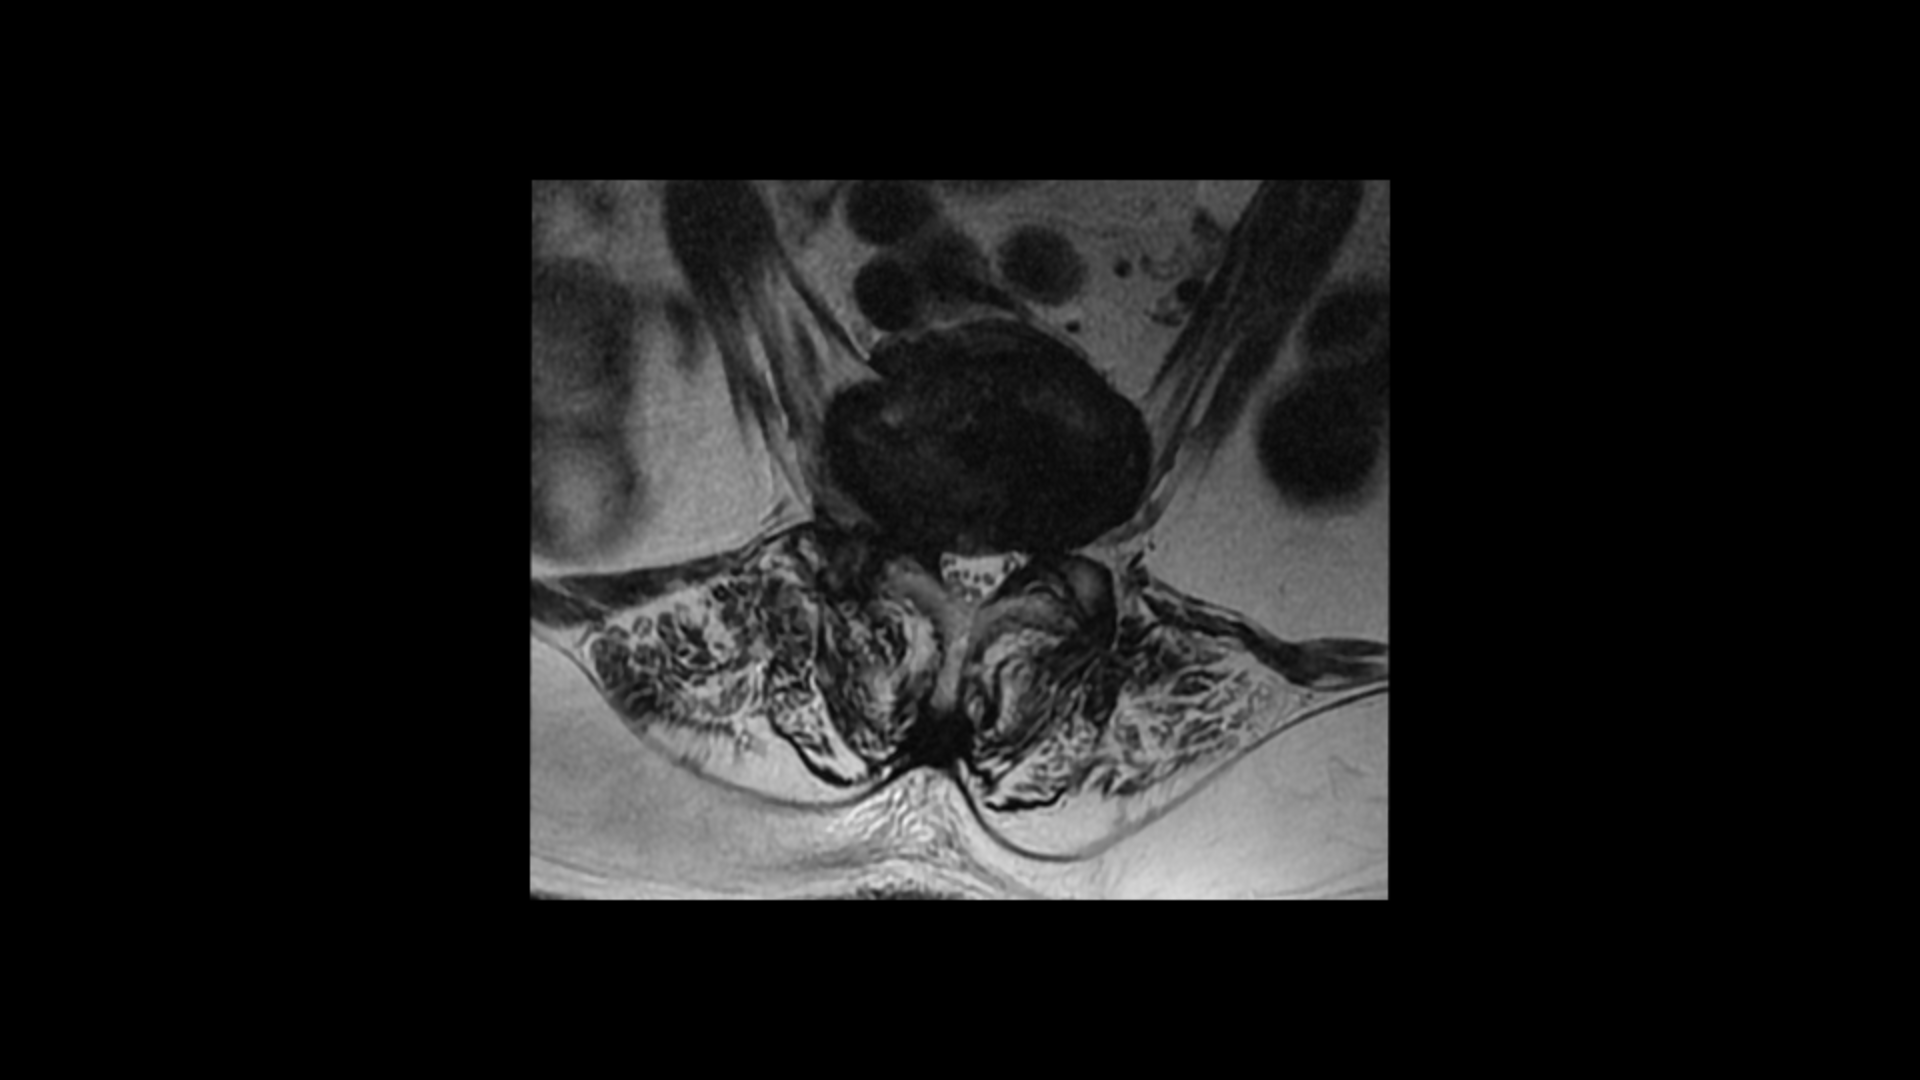

이분 MRI를 보면 보시다시피 허리의 5마디가 전부 퇴행이 진행되어 있습니다.

우선 전방전위가 2마디에 있고

여러 마디 2번 3번, 4번 5번에 척추관협착이 있고

2번 3번, 4번 5번, 오른쪽 신경가지가 빠져나가는 구멍들이 다섯 마디 전부가 다 오른쪽 좁아져 있습니다.

이분의 오른쪽 엉치와 다리가 저리고 아픈 원인은 이것 때문인 걸로 보입니다.

그런데 이분은 허리도 굽으셨는데 척추근육, 특히 허리를 세워주는 기립근을 mri에서 보면 허리 다섯 마디 전체에서 기립근의 근육이 지방으로 변해서 하얗게 보이는 지방화가 심합니다.

이렇게 근육이 지방으로 심하게 변하고 기능이 떨어지면 허리를 펴기가 어렵고 허리가 아플 수 밖에 없습니다. 여기 건강한 기립근과 비교해서 보면 그 차이를 금방 알 수가 있습니다. 기립근 크기도 차이가 크고 하얗게 지방으로 변해버린 부분을 잘 보실 수 있습니다.